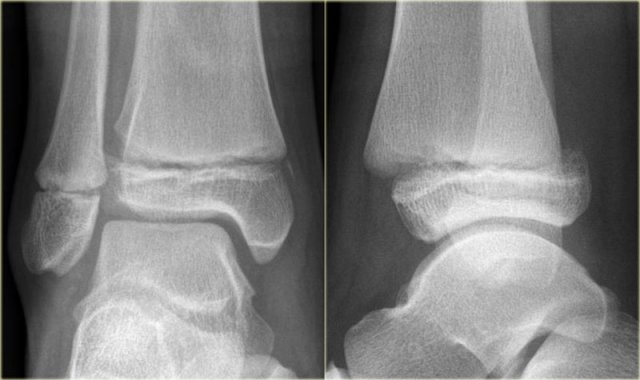

Triplane fracture Triplane fracture

At first this looks like a Weber B fracture with an oblique fracture in the fibula as seen on the lateral view (black arrows).

Notice however that this fracture line stops at the level of the epiphyseal plate.

So this is the fracture of the metaphysis in the coronal plane.

On the AP-view there is a lucency within the epiphysis, which is the epiphyseal fracture in the sagittal plane.

Notice also that the medial epiphysis is already closed, while the lateral portion is still open(blue arrows).

We have to assume that there is an epiphysiolysis of this lateral portion.